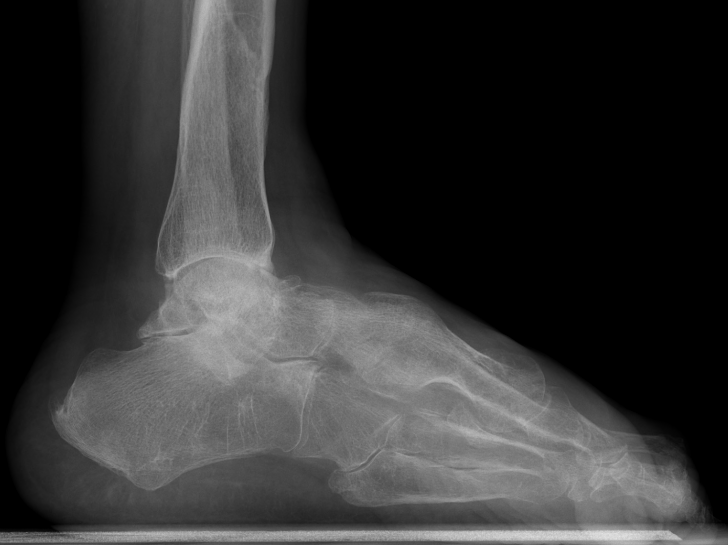

Combined ankle and subtalar joint osteoarthritis

Talar AVN

Severe Deformity - acquired flat foot / neurological conditions / Charcot /

Severe acquired planovalgus